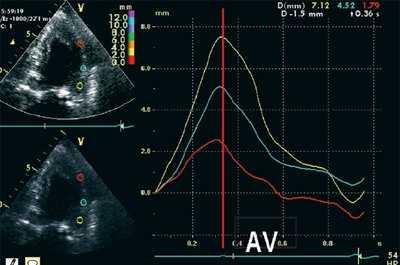

На рис. 3-5 приведены различные варианты ПСУ у больных с постинфарктным кардиосклерозом.

![Кривые деформации миокарда в норме]()

![Кривые деформации миокарда при постинфарктном кардиосклерозе]()

б) При постинфарктном кардиосклерозе. У больного регистрируется высокоамплитудный пик постсистолической деформации (STps).

Вертикальная линия (AV) на рис. 3-5 соответствует времени закрытия аортального клапана. На представленных графиках также отмечается наличие базально-верхушечного градиента (снижение пиковых миокардиальных скоростей, продольного систолического смещения и деформации от основания к верхушке левого желудочка).